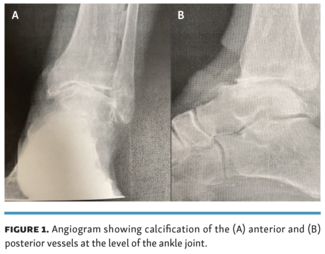

Vikrant Wadehra, DPM; Guy R. Pupp, DPM, FACFAS; Jihad A. Mustapha, MD, FACC, FSCAI

The following case report follows a 78-year-old male with CLI who underwent invasive total ankle joint replacement.